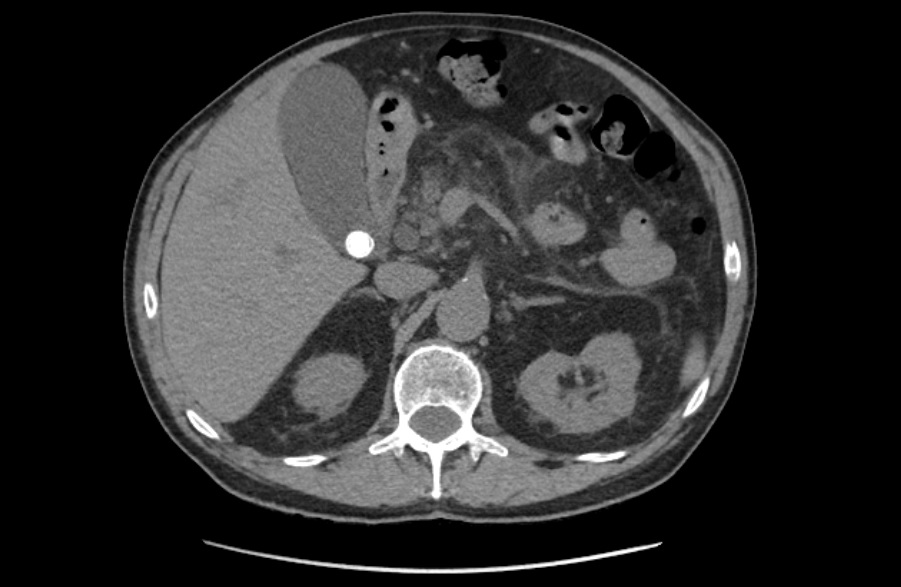

La litiasis y la dilatación de la vesícula biliar encontrada en la ecografía clínica no justificaba todo el cuadro, por lo que solicitamos ecografía reglada al equipo de radiología. En ella informan marcada dilatación de la vía biliar intrahepática, con un colédoco de hasta 15 mm, y estructura mamelonada de aproximadamente 7 cm en cabeza pancreática. Se completa estudio con Tomografía Axial Computarizada que confirma masa en cabeza pancreática compatible con adenocarcinoma que condiciona dilatación de la vía biliar retrógrada.